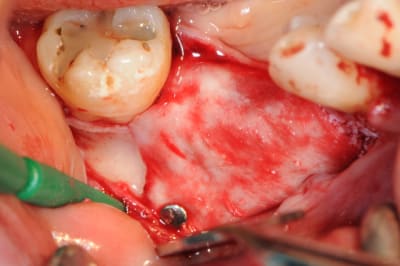

CAS 1

demande de restauration avec implant, mais, ne veut pas entendre parler de greffes et greffons.

la ROG lui semble plus "naturel".

1-2-3 situation de départ

4 après ouverture